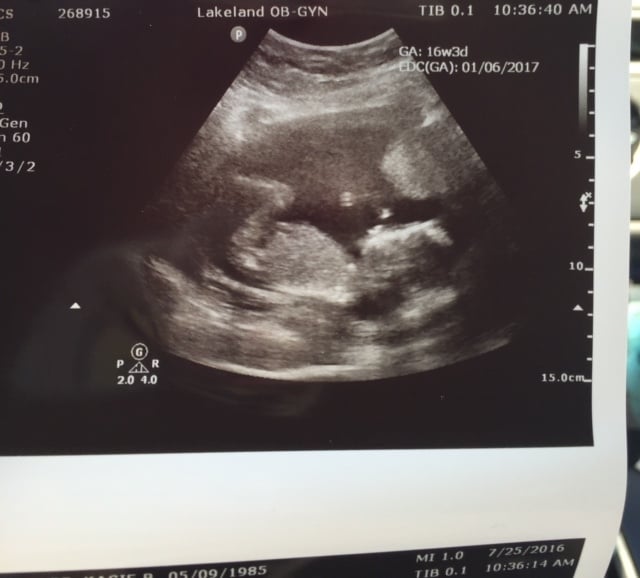

R/R/Other: I have a Wusic at home doppler, and have been able to hear the heartbeat for the last 3 weeks. Yesterday, my dad came to my house and wanted to hear the heartbeat, and I couldn't find it. I tried not to freak, and listened again before I went to bed, and still nothing. I checked before I went to work this morning, and and still couldn't hear anything. So, I panicked. I put an email in to the nurse on call, and she called me and told me to come in right away. She checked me with their doppler for 15 minutes. Still nothing. They got me in with the ultrasound tech. Kitten was okay and has a heartbeat of 156. It was such a relief and I cried and cried and cried. The nurses were so sweet and I am so grateful. I am going to hide my doppler for the rest of my pregnancy.. it stresses me out too much, which is what I was afraid of when I bought it.

Here's a picture of Kitten kicking me today: